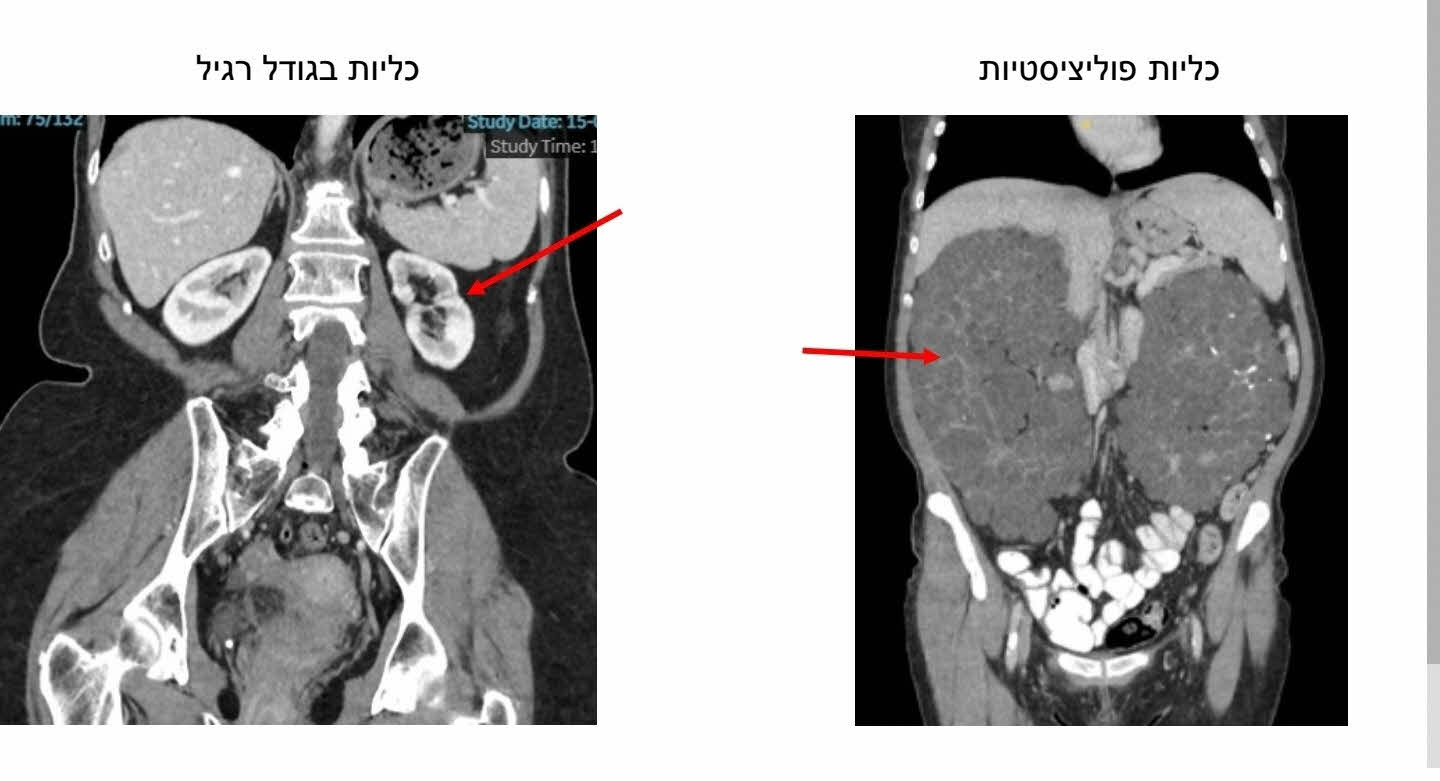

אוליאנה שבלה (51, סבתא ל-2 נכדים), נולדה עם מחלה גנטית בה רקמת הכליות הופכת לציסטות מרובות ובהדרגה מאבדות את תפקודן, עד מצב סופי ובלתי הפיך של כליות פוליציסטיות אשר אינן מסוגלות לבצע סינון תקין של הדם מרעלים. לאור זאת מזה כ-15 שנים, שבלה עוברת דיאליזה, 3 פעמים בשבוע, בבי״ח אסותא אשדוד. במקביל, בשנים האחרונות, הכליות שלה (לא תפקודיות) המשיכו לגדול והגיעו לממדים קיצוניים עד למילוי מרבית חלל הבטן. היא סבלה מכאבים קשים, זיהומים, בצקות וקושי במאמץ ודיווחה על פגיעה משמעותית באיכות החיים.

שתי הכליות יחד שקלו יותר מ-5 ק"ג. כאשר משקל כליה בריאה נע בין 120 ל־170 גרם בלבד.

אורכן של הכליות הגיע ל- 35 ס״מ לעומת כ 10 ס״מ בכליות בריאות.

טווח המשקל המקובל של כליות פוליציסטיות נע בין כ־1.6 ל־2.4 ק"ג – מה שהופך את המקרה הנוכחי לנדיר במיוחד.

מדובר במקרה נדיר ביותר, כאשר אחת הכליות הפוליציסטיות שהוסרו נמנית עם הגדולות שתועדו בספרות המקצועית בשנים האחרונות.